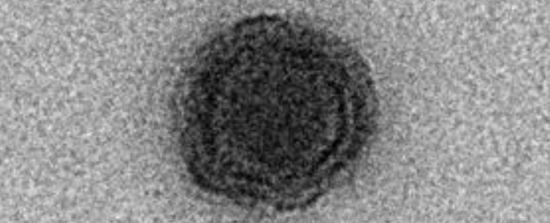

Ученые из США завершили тестирование вакцины против вируса герпеса, который проявляет себя на губах (ВПГ-1). Ее создали на основе генно-модифицированной формы вируса. Об этом пишет портал NEBRASKA TODAY.

Чтобы решить эту проблему, ученые разработали генно-модифицированную форму вируса, которая предотвращала его проникновение в нервную систему.